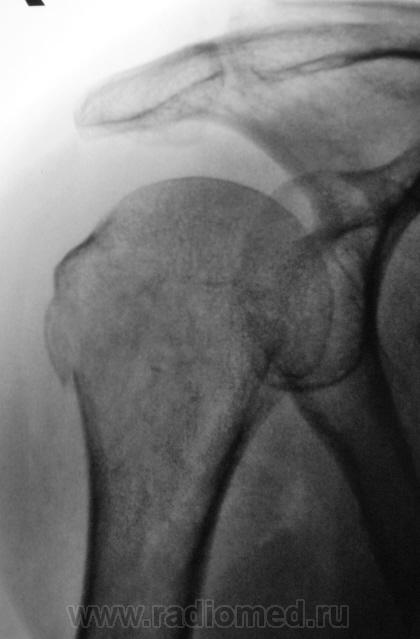

Сегодняшний случай.

1..H.P..JPG2..H.P..JPG3..H.P..jpg